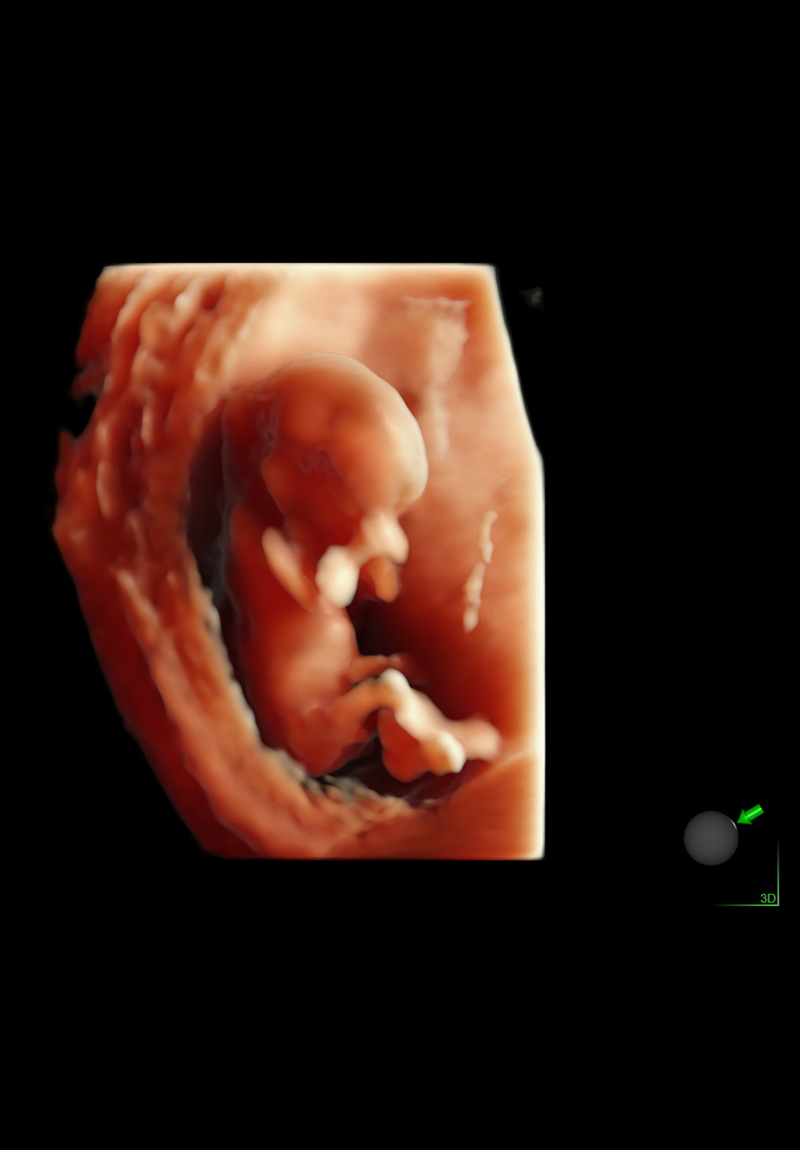

Eco Anatómico 4D

Realizado entre las semanas 20 y 30, el Eco Anatómico 4D, es un estudio que permite una valoración detallada del crecimiento, órganos y estructuras de bebé. Este eco es crucial para la detección temprana de malformaciones congénitas. Si la posición de bebé y las condiciones nos permiten, podemos llevarnos un hermoso recuerdo al tomar fotografías en 4d.